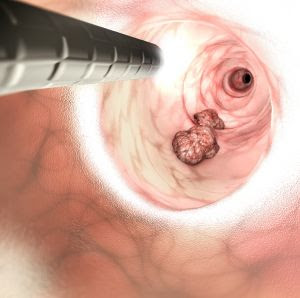

O câncer colorretal (intestino grosso/cólon e reto), causa da internação de Pelé, resulta em 900 mil mortes anuais no mundo, atrás apenas do câncer de pulmão. No Brasil, a doença é o segundo câncer mais comum em homens e mulheres, com 45.630 novos casos anuais

O cirurgião oncológico e presidente da SBCO, Héber Salvador, explica que o câncer colorretal pode se desenvolver silenciosamente por um tempo, sem apresentar nenhum sintoma e a descoberta, muitas vezes, se dá por exame de rastreamento. “É fundamental a realização de colonoscopia a partir dos 50 anos em pessoas sem sintomas– ou 40 anos, caso haja histórico de câncer na família. Este exame pode evitar a doença, pois, por meio dele, é possível retirar pólipos, que são lesões presas na parede do intestino que poderiam evoluir para câncer”, explica.

Quando descoberto em fase inicial, ainda restrito ao local de origem, o câncer colorretal tem taxa de cura acima de 90%. Quando se espalhou para os linfonodos, a taxa cai para 70%. Em caso de metástase, as chances de cura não chegam a 20%. “Quando um tumor originado no cólon (intestino grosso) se espalha, o órgão que mais apresenta metástase é o fígado”, explica Héber Salvador.

O câncer colorretal pode se desenvolver silenciosamente por um tempo, sem apresentar nenhum sintoma. Quando o paciente apresenta sintomas, já pode ser sinal de uma doença mais avançada. Por conta disso, é fundamental a realização de colonoscopia a partir dos 50 anos em pessoas – ou 40 anos, caso haja histórico de câncer na família. Este exame pode evitar a doença, pois, por meio dele, é possível retirar pólipos, que são lesões presas na parede do intestino que poderiam evoluir para câncer.

QUAIS SÃO AS CAUSAS DO CÂNCER COLORRETAL?

Ainda que possa se desenvolver em jovens, o câncer colorretal é mais comum a partir dos 50 anos. Por isso, a idade é tida como um dos pontos de atenção ao surgimento da doença. Mas não é só. Os principais fatores de risco para o câncer colorretal:

QUAIS SÃO OS SINAIS DO CÂNCER COLORRETAL?

Como dissemos há pouco, o câncer colorretal, em seu estágio inicial, raramente apresenta sintomas específicos. Ainda assim, podem aparecer alguns sinais que indicam alterações e merecem atenção, especialmente para pessoas que se enquadram nos fatores de risco descritos anteriormente. Assim, vale ficar atento à:

Se apresentar algum desses sinais de forma frequente, é importante passar pela avaliação de um médico especializado. Além do câncer, estas ocorrências podem indicar a presença de outras doenças que também precisam de tratamento.

Como o câncer é uma doença multifatorial e tem, entre seus causadores, a predisposição genética, não existe uma conduta que garanta 100% a sua prevenção. No entanto, ao evitar os fatores de risco, a possibilidade de desenvolver o câncer colorretal fica menor. A alimentação tem grande influência na prevenção do colorretal. Nesse sentido, nosso conselho é manter a saúde em dia, investindo em qualidade de vida, com algumas medidas como:

COMO É O TRATAMENTO DO CÂNCER COLORRETAL?

O primeiro passo para o tratamento do câncer colorretal é, em geral, a cirurgia oncológica. Em alguns casos, a cirurgia pode ser seguida pela radioterapia e a quimioterapia. Vale lembrar que o câncer é uma doença complexa, que pode exigir abordagens diferentes de caso a caso. Por isso, toda a definição do tratamento, bom como das condutas terapêuticas e do tipo de cirurgia realizada, depende do momento da detecção da doença.

Quando o diagnóstico é precoce, as chances de cura são significativamente maiores e o tratamento se torna mais simples, já que o tumor ainda está em sua fase inicial. Em todos os casos, a equipe multidisciplinar determina a conduta ideal, baseando-se na extensão da doença.